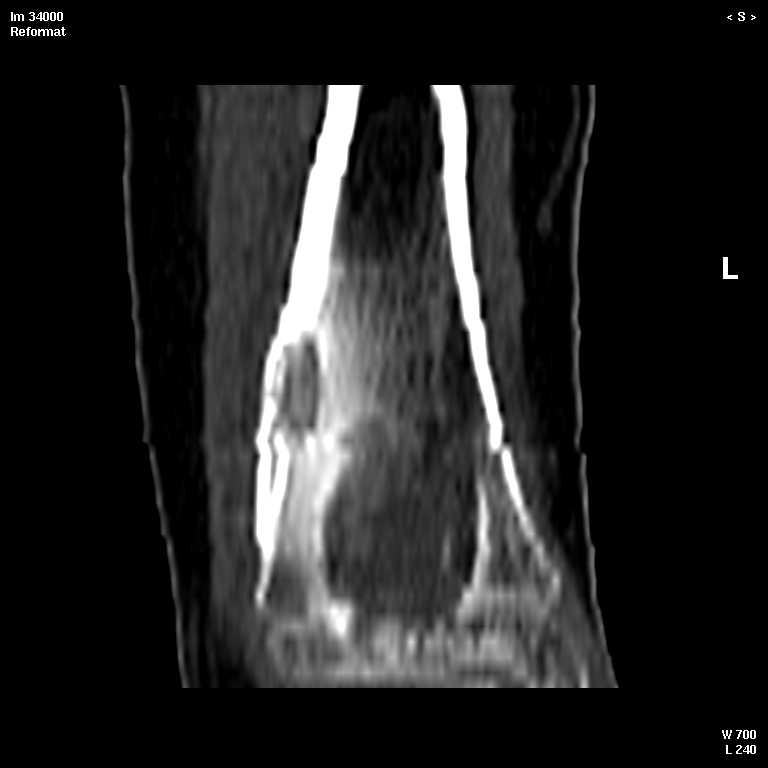

В обсуждении темы возникла необходимость дополнительных данных.

КТ изображения передаю на мой взгляд самые демонстративные. Их любезно записал коллега,

проводивший исследование в другом городе.